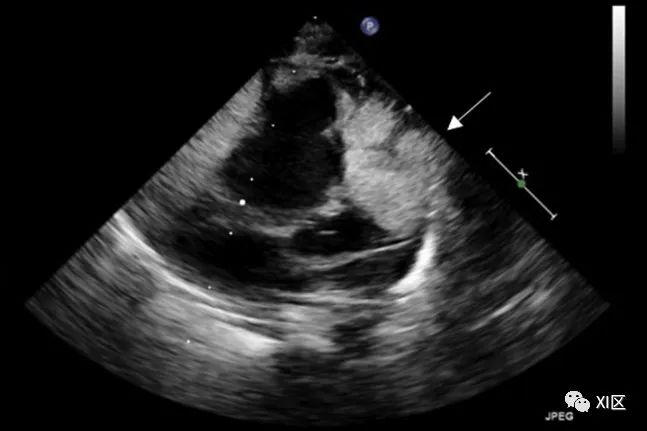

横纹肌瘤(图 5)是最常见的小儿 PCT,通常在婴儿出生后第一年发病。这些肿瘤在 90% 的患者中为多发,通常累及心房和心室,在心脏左右两侧的分布相同。横纹肌瘤与结节性硬化症的关系已得到证实。横纹肌瘤具有心律失常性,可出现心悸和晕厥症状。导致血流受阻的腔隙突出可能会导致心力衰竭症状。

图 5 横纹肌瘤产前诊断为多发性心脏横纹肌瘤的新生儿的超声心动图,该新生儿随后被诊断为结节性硬化症。大的心脏肿块向右心室壁侧面、后方和前方延伸,但无右心室流出道梗阻的证据。

在 TTE 上,这些肿块可能表现为圆形(多发)小结节或心腔内有蒂的肿块。偶尔会出现心肌包埋,表现为分叶的均质和高回声肿块,通常比周围心肌更亮。心脏 CT 通常会显示具有均匀低衰减和腔内扩展的膜内病变。多发性肿块和结节性硬化的其他特征可将横纹肌瘤与纤维瘤区分开来。在 CMR 的 T1 加权成像中,横纹肌瘤可表现为等信号,而在 T2 加权成像中,与心肌相比,横纹肌瘤往往表现为高信号。横纹肌瘤没有延迟钆增强表现。